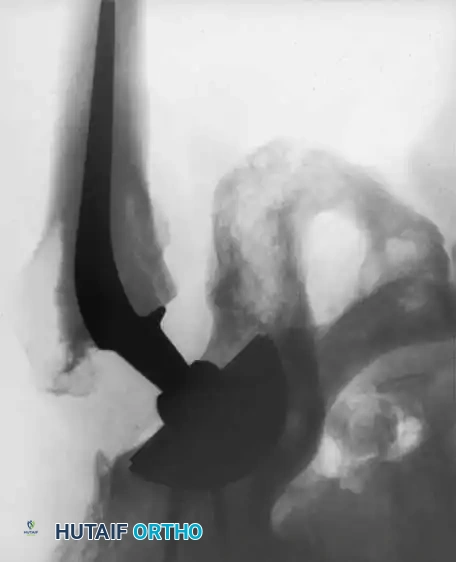

Surgical Technique and Prior Graft Management

Upon capsulotomy, the surgeon will often encounter a highly hyperemic capsule and profound synovial proliferation. A large synovial effusion is common and should not immediately be mistaken for infection, though routine cultures are prudent. Meticulous hemostasis is required.

Pitfall: If the patient has previously undergone a cortical bone grafting procedure (e.g., free or vascularized fibular graft), the intramedullary portion of the graft must be completely excised. Conventional broaches will deflect off the hard cortical graft, leading to varus malpositioning and undersizing of the femoral component.

To safely remove prior grafts, the surgeon should utilize a high-speed burr and flexible reamers. Intraoperative fluoroscopy with the broach in place is highly recommended to ensure complete graft removal, proper alignment, and optimal cortical contact.

Radiographic Case Examples: Osteonecrosis and Complex Femoral Reconstructions

Advanced osteonecrosis with subchondral collapse and secondary arthritis.

Intraoperative imaging showing retained fibular graft from a previous joint-preserving procedure.

Use of a high-speed burr to clear the intramedullary canal of sclerotic graft remnants.

Fluoroscopic confirmation of proper broach alignment after graft removal.